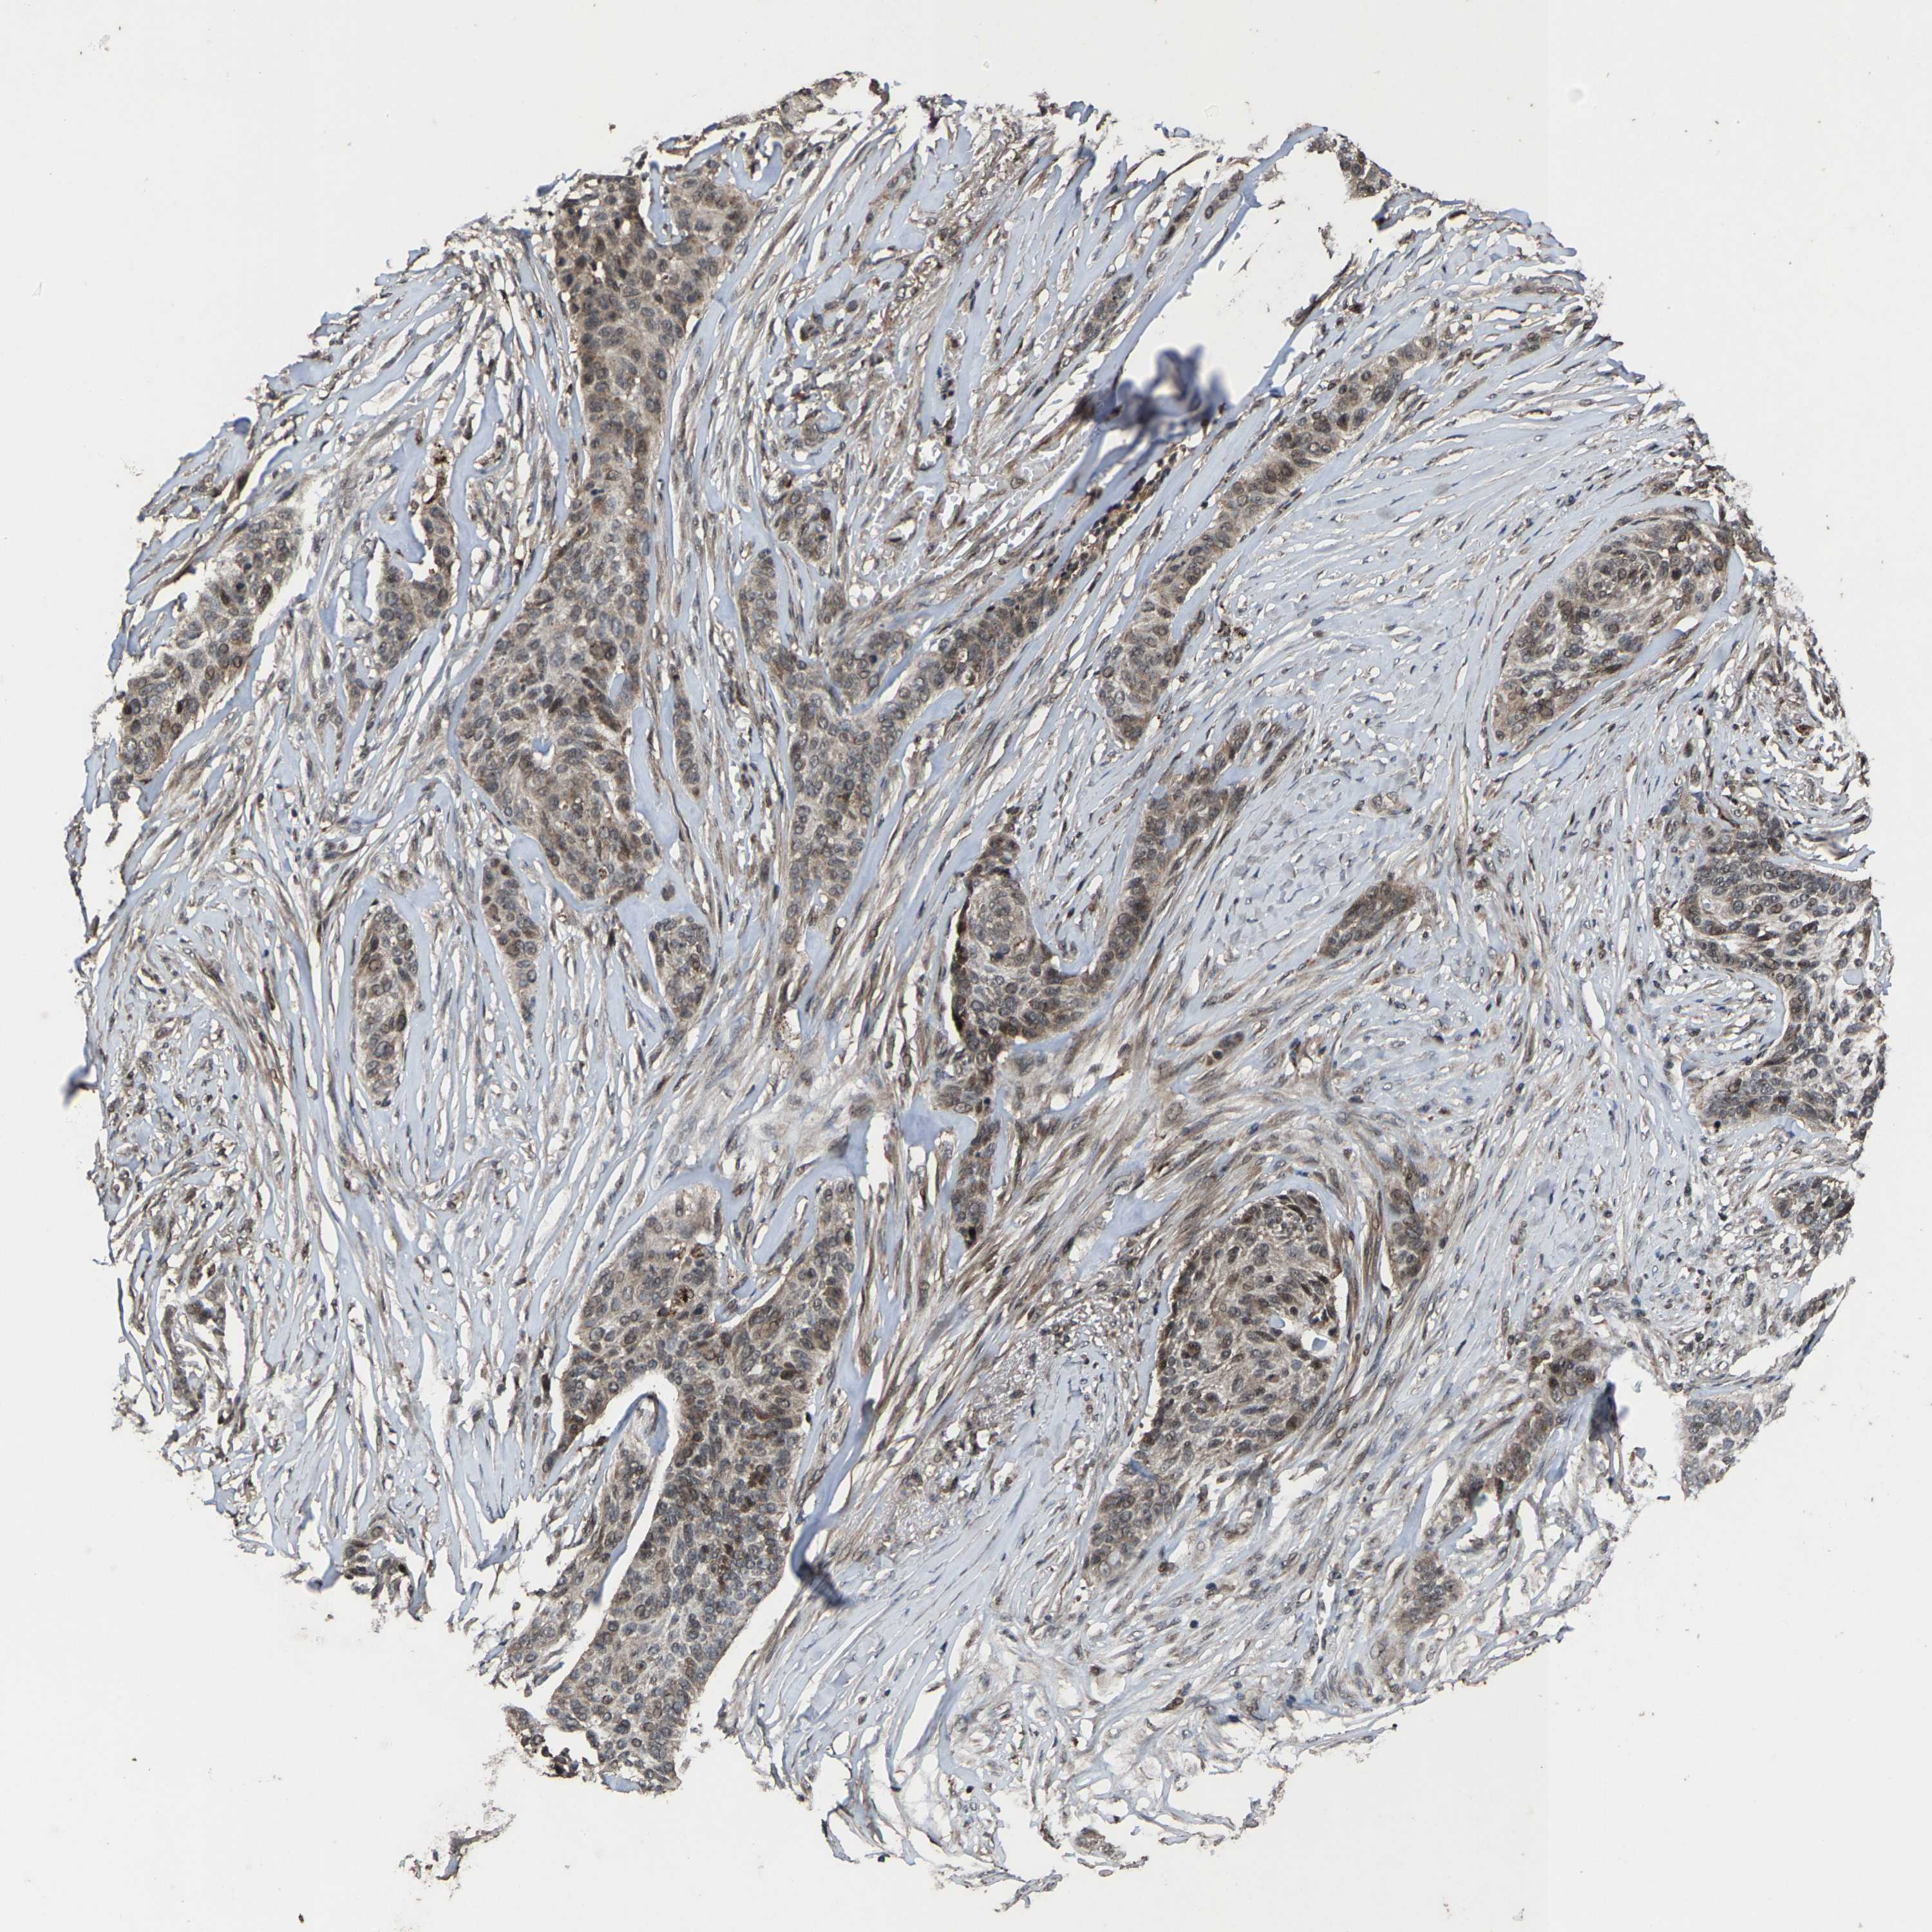

Basal cell and squamous cell cancer

SKIN CANCER - Protein expressioni

A mouse-over function shows sample information and annotation data. Click on an image to view it in a full screen mode. Samples can be filtered based on level of antibody staining by selecting one or several of the following categories: high, medium, low and not detected. The assay and annotation is described here.

Antibody stainingi

Antibody staining in the annotated cell types in the current human tissue is reported as not detected, low, medium, or high, based on conventional immunohistochemistry profiling in selected tissues. This score is based on the combination of the staining intensity and fraction of stained cells.

Each image is clickable and will lead to virtual microscopy that enables deeper exploration of all samples and also displays staining intensity scores, fraction scores and subcellular localization as well as patient and tissue information for each sample.

Antibody HPA020960

Antibody HPA020965

Staining

High

Medium

Low

Not detected

Intensity

Strong

Moderate

Weak

Negative

Quantity

>75%

75%-25%

<25%

None

Location

Nuclear

Cytoplasmic/membranous

Cytoplasmic/membranous,nuclear

Basal cell carcinoma

Squamous cell carcinoma, NOS

Squamous cell carcinoma, metastatic, NOS